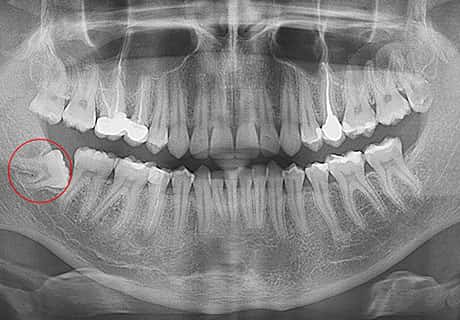

Атипове розташування зуба